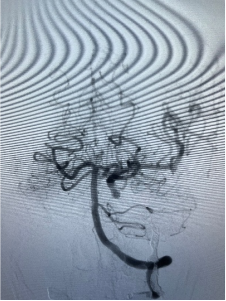

由于内镜下止血困难,考虑鼻咽癌治疗后并发颈内动脉爆裂综合征大出血,治疗团队立即将患者转入复合手术室。此时,神经外科脑血管病团队早已枕戈待旦,无缝衔接开始手术。面对患者大出血的危急情况,神经外科昝春树主治医师来不及穿戴铅衣,一头扎进抢救工作。股动脉穿刺,微导管、超滑导丝导引导管迅速超选至左侧颈内动脉等系列操作一气呵成。术中造影证实了左侧颈内动脉假性动脉瘤破裂出血,像一股洪流一样持续向外喷出。

快速闭塞血管后无出血

后交通动脉开放 代偿左侧大脑中动脉供血

“患者左侧颈内动脉后交通动脉粗大,假性动脉近远端已经发生夹层改变。”手术团队凭借丰富的经验,果断决策闭塞左侧颈内动脉,选择大而长的弹簧圈在假性动脉瘤近远端闭塞颈内动脉,成功止住出血。取出咽喉部压迫棉片及棉条均无活动性出血,继续输血、输血浆,予以抗休克治疗。全脑血管造影显示,后交通动脉代偿良好,左侧大脑中动脉血流速度正常,眼动脉显影良好,患者的生命体征逐步恢复正常。见患者情况逐渐平稳,所有人都松了一口气。